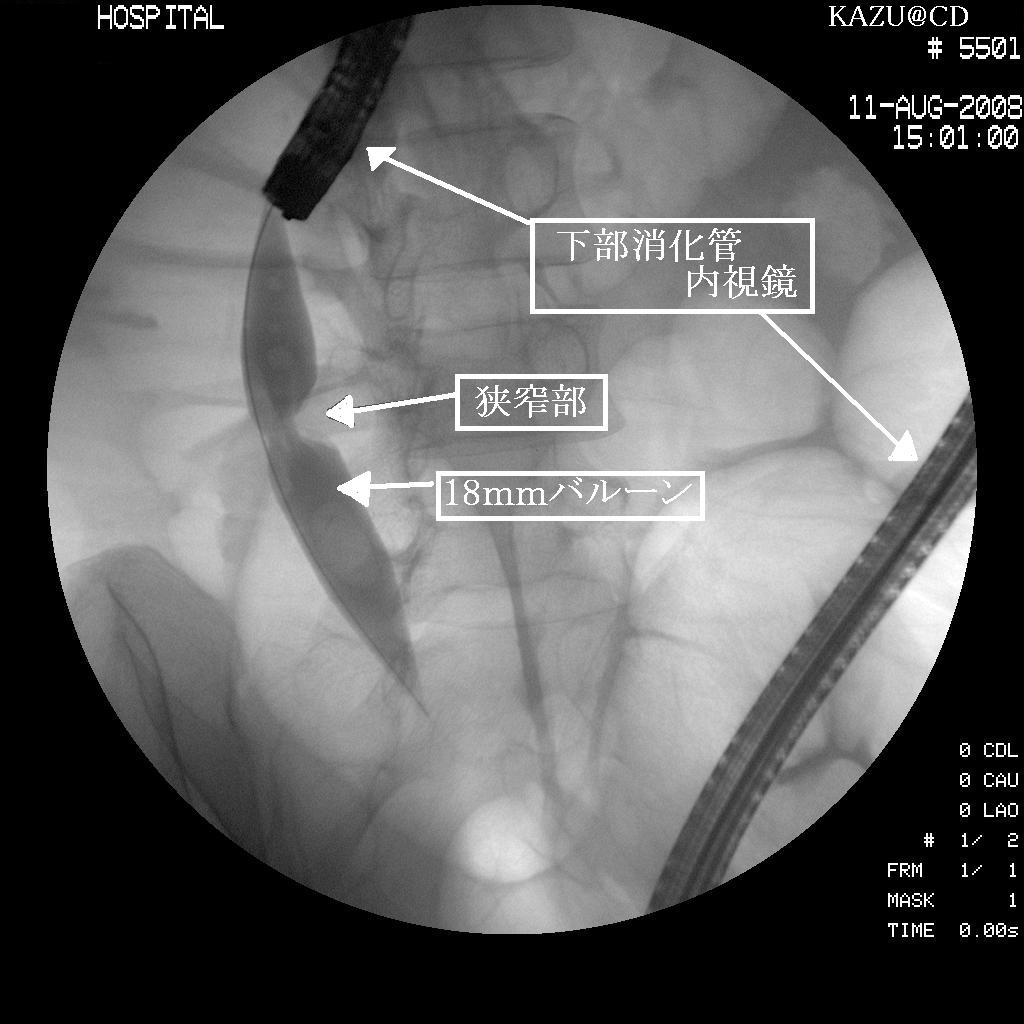

今回も画像を頂いてきたがスキャンの調子が悪いので前回の画像を載せときます

(2008年8月の画像)

白い半透明な物がバルーンです

レントゲンの画像も前回の分です

バルーンを膨らまします